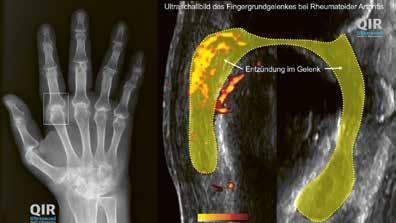

Sopra: articolazione metacarpofalangea sana in una radiografia (sinistra) ed ecografia (destra).

Sotto: articolazione metacarpofalangea colpita da AR in una radiografia (sinistra) ed ecografia (destra).

Esami complementari

In seguito, in genere la diagnosi viene verificata sulla base di esami di laboratorio, ecografie o radiografie. Tali esami hanno il fine di escludere altre patologie e valutare meglio la gravità e il probabile decorso dell’artrite reumatoide.

La presenza nell’emocromo di valori infiammatori elevati, del tipico fattore reumatoide e degli autoanticorpi (anticorpi anti­CCP) indica un’elevata attività della malattia

13 Aspetti medici

(ricaduta) e possibilmente un decorso con una prognosi peggiore. L’ecografia è volta a individuare l’ispessimento della membrana sinoviale, l’aumento del liquido sinoviale e dell’irrorazione sanguigna nell’articolazione nonché piccoli danni sulle ossa vicine all’articolazione. Questi piccoli punti danneggiati si chiamano erosioni. Le radiografie sono in grado di accertare se le mani e i piedi presentano erosioni e segni di osteoporosi, che viene favorita dai processi infiammatori. Al più tardi dopo un anno si effettua il confronto con lo stato precedente per verificare se la malattia è sotto controllo o se il trattamento va intensificato o modificato.